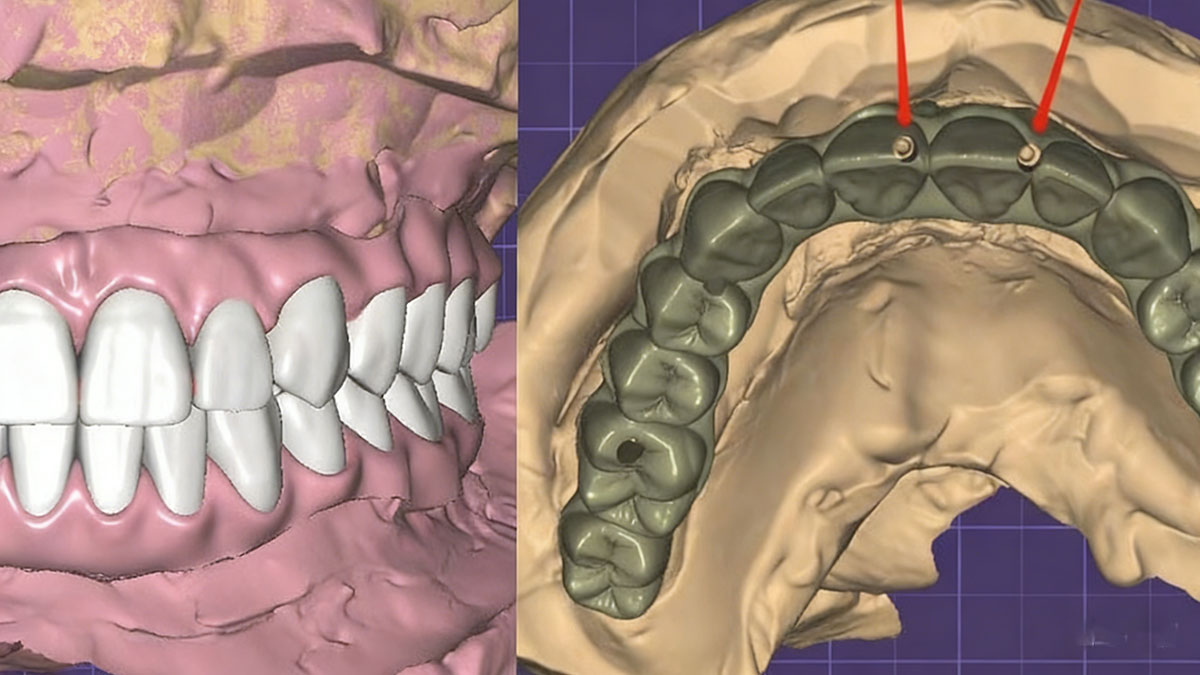

About 5 days later, we received stone models, the titanium bars, temporary bridges, and a new bite registration. With the help of pictures and new bite registration from our doctor, we re-designed titanium bars and temporary bridges.

4. New titanium bar with new temporary bridges

At this stage, we could normally just finish the case by making the permanent restorations: the mid-line would be fine because of the help of pictures and temporary bridges. Yet, the doctor wanted to try mid-line again. After having approval of the new designs from our doctor, we milled new titanium bars and temporary bridges again.